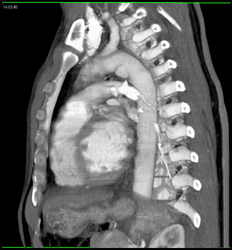

Diagnosis

Tibial Fracture